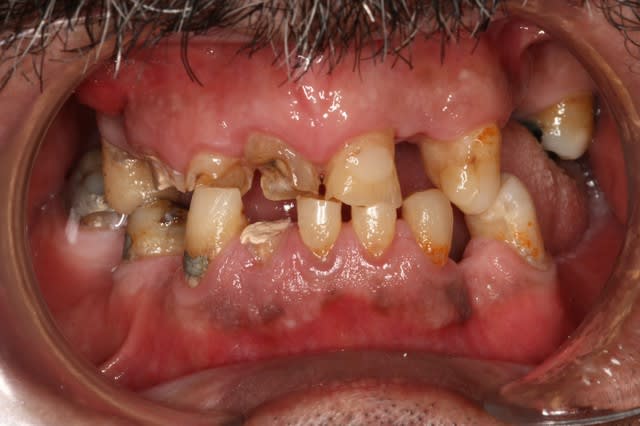

Autre photo et une radio

Occlusion pr  op cgna2r - Eugenol

Radio montage rdhjbj - Eugenol